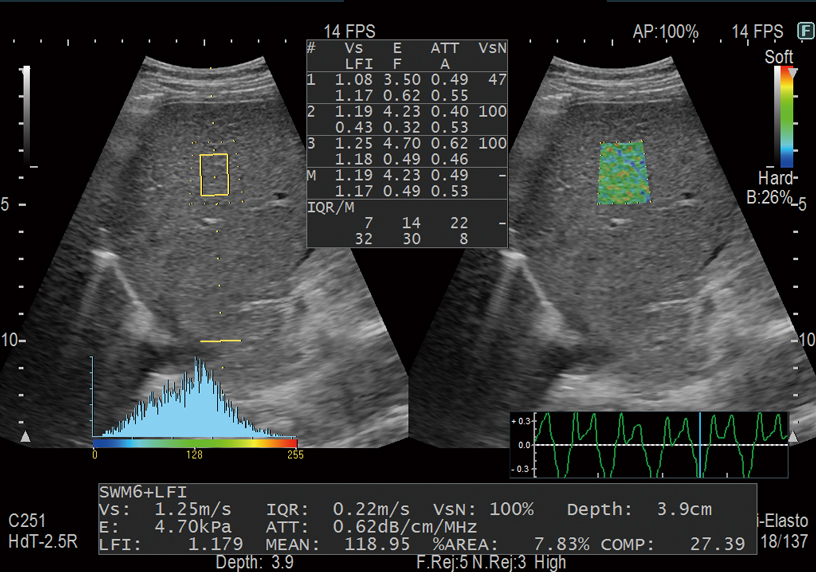

Messung des Leberfettgehaltes mithilfe des ATT-Index.

Durch die Integration der beiden nicht-invasiven Methoden zur Bewertung der Steifigkeit des Lebergewebes, nämlich RTE und SWM, ist es möglich, das chronologische Fortschreiten von Leberentzündung und Fibrose mit größerer Genauigkeit zu beurteilen. Eine kombinierte gleichzeitige Schätzung des Steatosegrades (ATT-Index) macht Combi-Elasto zu einem umfassenden Instrument für die Differentialdiagnose von Lebererkrankungen.